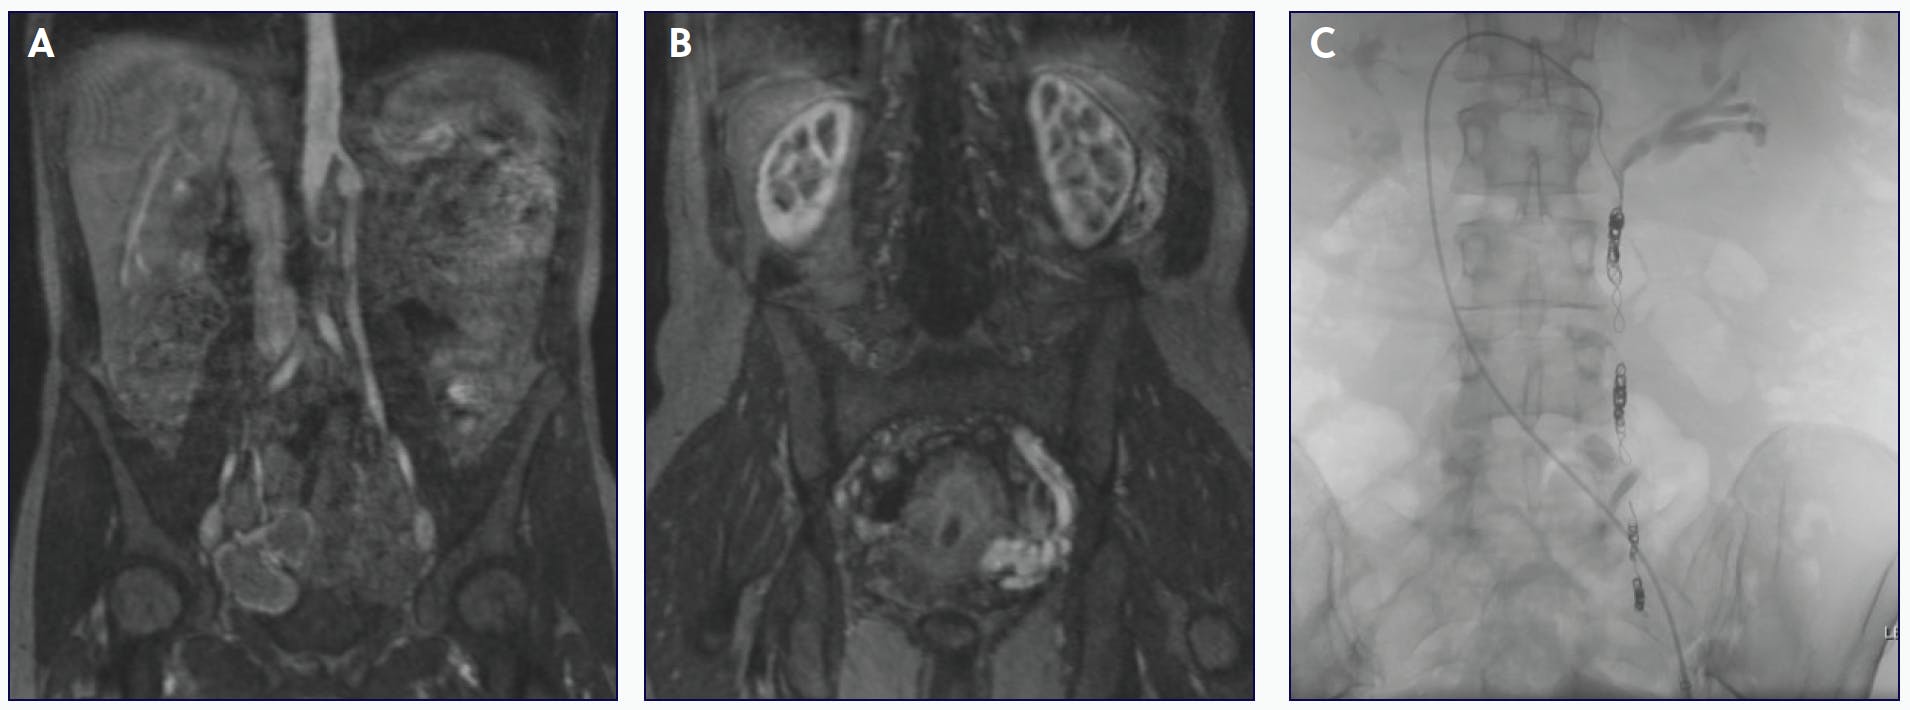

A female patient in her 30s presented to our clinic with a history of many years of debilitating pelvic pressure and pain, especially pronounced on the left side. She also reported bulging vaginal and vulvar varicosities, left lower extremity varicose veins, and increasingly worse pelvic pain after intercourse. She reported some relief with nonsteroidal anti-inflammatory drug treatment. The patient underwent an abdomen/pelvis MRV that showed an enlarged left gonadal vein and left pelvic varices abutting the uterus (Figure 2A and 2B). The SVP classification was S2V2PLGV,R,NT. The decision was made to proceed with left gonadal vein embolization and sclerotherapy of pelvic varicosities given the patient’s presentation (Figure 2C). At 4 weeks and 3 years postprocedure, the patient reported a significant improvement in pelvic pain and remained symptom free.

Figure 2. MRV shows a dilated left gonadal vein (A) with left-sided pelvic varices (B). The patient underwent successful left gonadal vein embolization with the 6-8–mm Concerto™ Helix detachable coil system (Medtronic), following sclerotherapy of the pelvic varices (C).